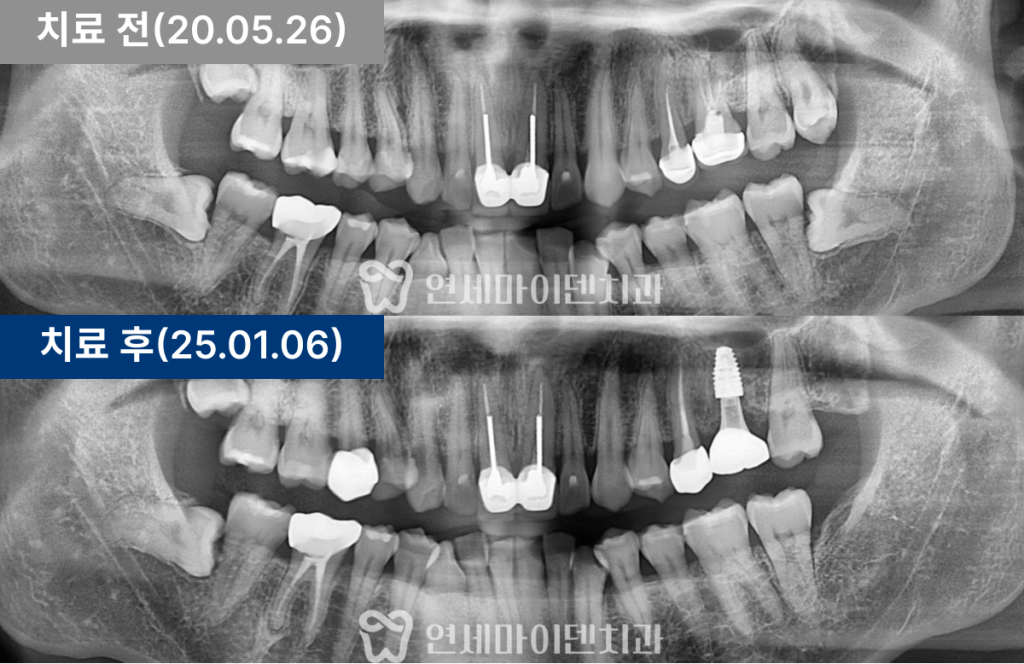

환자 증상과 진단 과정

환자분은 “왼쪽 위 어금니가

시리고 아프다”고 호소하셨습니다.

#25번과 #26번 두 치아 모두 과거

신경치료를 받은 상태였으며,

염증이 관찰되었습니다.

파노라마와 CT를 함께 분석하여 정확한 원인을 찾았습니다.

치료 경과 및 예후

3년간의 추적 관찰 결과, #26번 임플란트는

주변 잇몸과 뼈의 안정성이 매우 양호한 상태로 유지되고 있습니다.

#25번 재신경치료 부위 역시 염증이 완전히 소실되어,

통증 없이 자연치아처럼 사용 중이십니다.